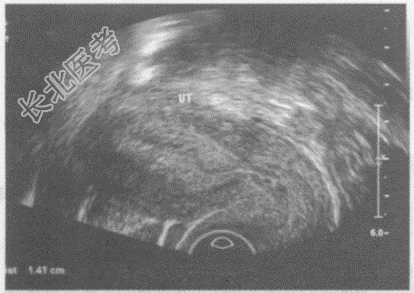

- 单项选择题临床资料:女性患者, 29岁,自诉月经不规律。

超声综合描述: 纵切面可见两个独立完整的子宫,均有完整的内膜、肌层、浆膜层, 内膜厚度1.4cm。横切面见两子宫间有凹陷,两宫体并列呈蝴蝶状, 宫颈及阴道完全分开。

超声提示: A、完全纵隔子宫

B、残角子宫

C、双子宫

D、双角子宫

E、鞍状子宫